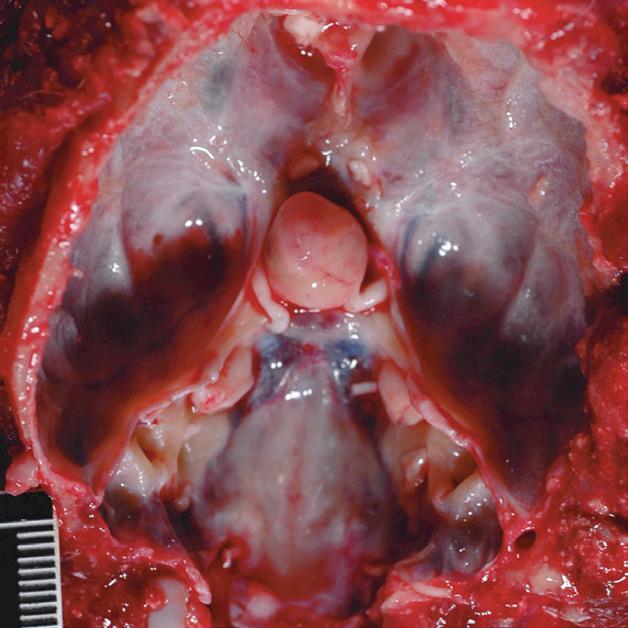

Badanie wykonano u 14-letniej, kastrowanej samicy szpica z przechyleniem głowy i występującym od niedawna chodzeniem w kółko w prawą stronę. Ryciny a–c to reprezentatywne obrazy w płaszczyźnie poprzecznej na poziomie dołu przysadki. Ryciny d–f to analogiczne obrazy w płaszczyźnie strzałkowej. Przysadka mózgowa była znacznie powiększona (wysokość = 10 mm, szerokość = 10 mm), izointensywna w obrazach T1-zależnych (a, d) i łagodnie hiperintensywna w obrazach T2-zależnych (b, e) w porównaniu z istotą szarą głęboką. Stwierdzono również poszerzenie układu komorowego (wentrikulomegalię), które może wynikać z częściowej niedrożności. Przysadka uległa jednorodnemu wzmocnieniu kontrastowemu (c, f), a w badaniu pośmiertnym wykazano, że miała postać dobrze odgraniczonej, kulistej masy (g). Potwierdzono, że zmiana była makrogruczolakiem przysadki